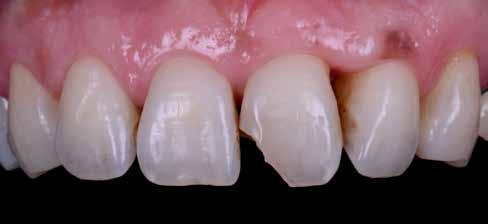

A fogászati kezelések során manapság már nem kizárólag az esztétikai megjelenés helyreállítására törekszünk. Sokszor a kedvezőtlen esztétikai megjelenés hátterében álló okok következményes módon a fogazat funkcionális működését is károsítják, így a kezelések során ezeknek a helyreállításával is foglalkoznunk kell. A különböző funkcionális és esztétikai diszkrepanciák kezelésére számtalan módszer létezik, ám ezen fogászati beavatkozások mindegyikében közös, hogy a kivitelezésük során nagyon szoros együttműködésre van szükség a kezelést végző fogorvos és a munkáját segítő fogtechnikus között. Az alábbi esetbemutatás során egy fiatal hölgypáciens fogazatának héjak alkalmazásával történő esztétikai és funkcionális rehabilitációját szeretnénk ismertetni.

A 19 éves hölgypáciens azzal a kéréssel jelentkezett a rendelőnkbe, hogy szebb fogakat szeretne. Az első konzultáció alkalmával megkérdeztük, hogy mi zavarja leginkább a fogazatának jelenlegi megjelenésében, valamint azt is megbeszéltük vele, hogy milyen végeredmény elérése esetén lenne maradéktalanul elégedett. Ebben az esetben a kezelési célokat az alábbiakban határoztuk meg:

A páciens fogazata esztétikai megjelenésének és funkcionális működésének a lehető legtöbb, saját foganyag megtartása mellett történő helyreállítása (1. és 3. ábra).

A kezelés megtervezése során kifejezett jelentősége van annak, hogy jó kommunikáció legyen a páciens, a fogorvos és a fogtechnikus között. A páciens leendő fogazatának természetes megjelenését a kezelésben részt vevő team szakmai felkészültsége, gyakorlati tapasztalata és a kezelés sikerességének irányába történő elkötelezettsége biztosítja. A beavatkozások megkezdése előtt megtörtént a páciens anamnézisének a felvétele, valamint a klinikai kivizsgálását is elvégeztük. Ezt követően lenyomatokat készítettünk a kiindulási állapotról, majd a kiindulási helyzetet extra- és intraorális fotók segítségével is rögzítettük (13. a-c. ábra).

A kezelés során az jelentette a legnagyobb kihívást, hogy a héjakkal ellátott fogak élethűen utánozzák a természetes fogazat megjelenését. A fogpótlás színének, valamint a restaurátumok felszíni textúrájának és alakjának harmonikusan kell a páciens arcesztétikájához és karakteréhez illeszkednie.

A tényleges protetikai ellátás megkezdése előtt a páciens mosolygás közben látható fogait otthoni fogfehérítés keretei között a kérésének megfelelő A1-es fogszín eléréséig fehérítettük. A fehérítés során a későbbiekben héjakkal ellátásra kerülő fogak színén nem változtattunk. A fogak előkészítése részeként csupán a két felső nagymetsző (1.1,2.1) incizális élét kellett kismértékben redukálni. A többi felső front fog (1.3,1.2,2.2,2.3) nem került preparálásra.

A héjak átadását követően kialakuló állapot valósághű módon történő bemutatása érdekében próbapasztát alkalmaztunk (Try-In-Paste; Variolink® Esthetik Try-In-Paste, Ivoclar Vivadent) (11. ábra). A próba során ellenőrizzük a héjak színét, formáját és transzparenciáját. A próbapaszta alkalmazásának egyik lényeges pontja, hogy a paszta színe egyezzen meg a végleges beragasztás során alkalmazni kíván ragasztóanyag színével. A héjak végleges rögzítése során mindig adhezív rendszereket használunk.

nak megfelelően – előkészítjük (orthofoszforsavval történő savazás, lemosás, szárítás és bond réteggel történő fedés). Ezzel egyidejűleg a ragasztásra kerülő héjak is előkészítésre kerülnek (hidrofolysavval történő savazás, lemosás, szárítás, szilanizálás, bond réteggel történő fedés, és végül az alkalmazni kívánt ragasztóanyag felvitele). Ezután a héjakat a fogak felszínén egyesével pozicionáljuk, majd néhány másodpercen keresztül polimerizációs lámpa segítségével megvilágítjuk. Ezt követően a kifolyó ragasztófelesleget eltávolítjuk, majd elvégezzük a restaurátumok végső polimerizálását. A héjak végleges rögzítését követően az esetlegesen visszamaradt ragasztómaradványok eltávolításra kerülnek, valamint ellenőrizzük az okklúzió és artikuláció közben létrejövő fogérintkezéseket. Az optimális esztétikai eredmény biztosítása érdekében kiemelt jelentősége van a papillák helyreállításának (rózsaszín esztétika). A modern fogorvoslás egyik kiemelt célja a fehér- és rózsaszín esztétika közti harmonikus egyensúly megteremtése. A papillák színe, nagysága és szimmetrikus megjelenése meghatározó szerepet tölt be a rózsaszín esztétika kialakításában. Az íny lefutása ugyancsak rendkívül jelentős mértékben befolyásolja a páciens fogazatának esztétikus megjelenését.